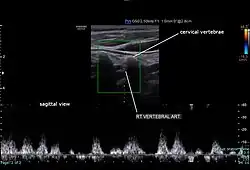

Sagittal section of the right vertebral artery on Doppler ultrasound

The condition and health of the vertebral carotid arteries is usually evaluated using Doppler ultrasound, CT angiography or phase contrast magnetic resonance imaging (PC-MRI).

Typically, blood flow velocities in the carotid artery are measured in terms of peak systolic velocity (PSV) and end diastolic velocity (EDV).[15]

Normally, vertebral artery blood flow velocity can be 63.6 ± 17.5 cm/s during PSV and 16.1 ± 5.1 cm/s during EDV according to a study done by Kuhl et al.[16] Due to vertebral artery dominance, measurements can vary on both sides, for example, another study by Seidel et al. found that the right side had an average of 45.9 cm/s and the left side 51.5 cm/s during PSV, and 13.8 cm/s on the right side and 16.1 cm/s on the left side during EDV.[15][17]